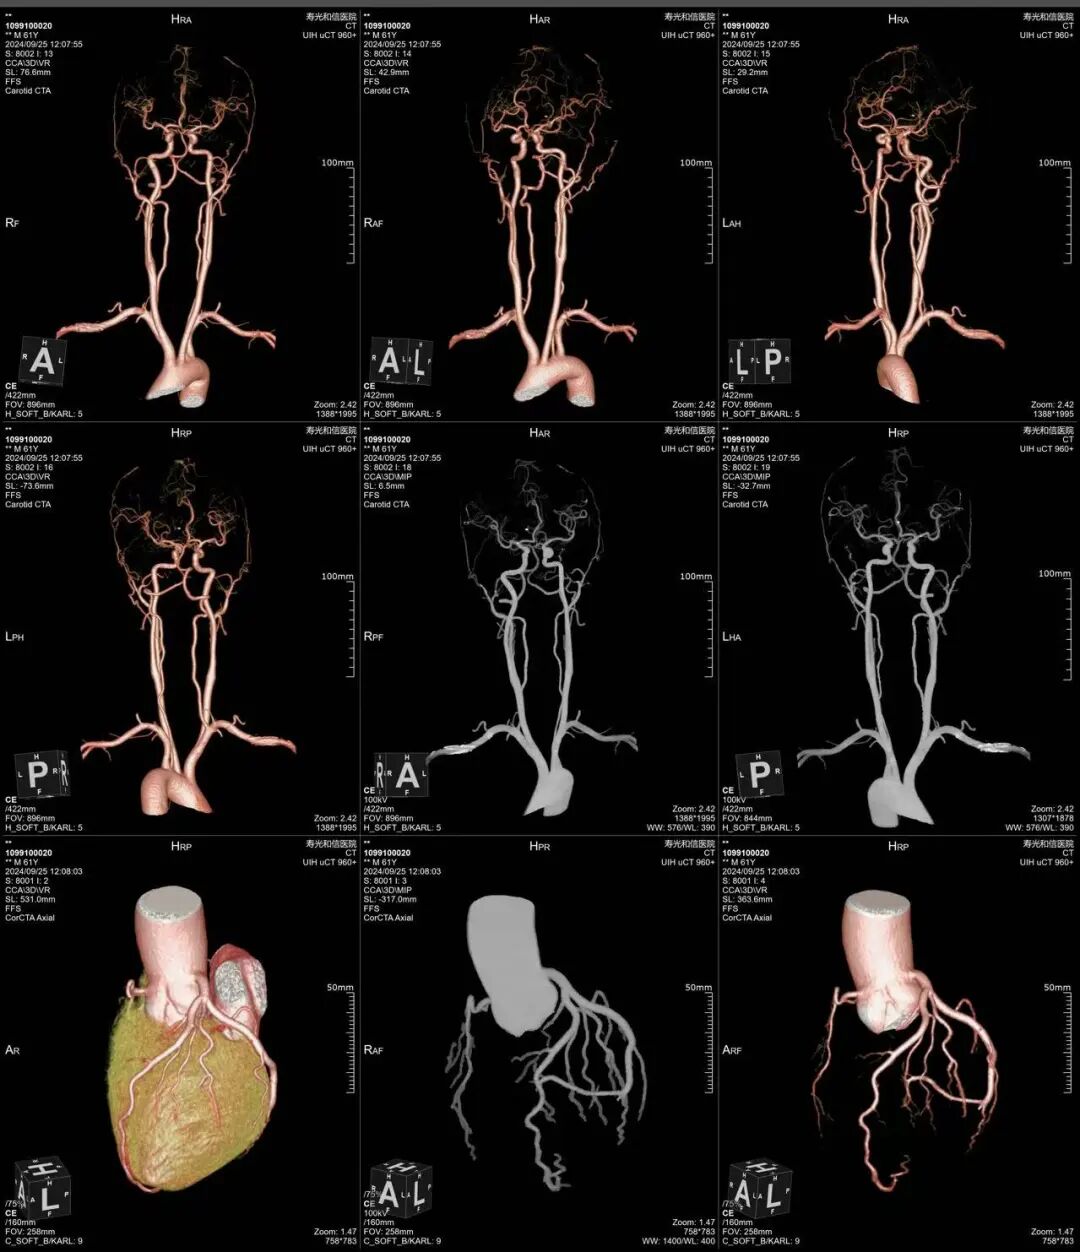

冠状动脉和头颈部动脉联合成像

640层意味着扫描极薄、极细腻,冠脉上有没有斑块、斑块是什么性质、狭窄程度多少,看得一清二楚。钙化、软斑块、混合斑块,都逃不过它的“眼睛”。

更重要的是,北京安贞医院的心血管专家定期来我院坐诊,亲自看片、亲自会诊,确保筛查质量。设备先进+专家把关,为民众的心脏健康提供全方位的专业保障。